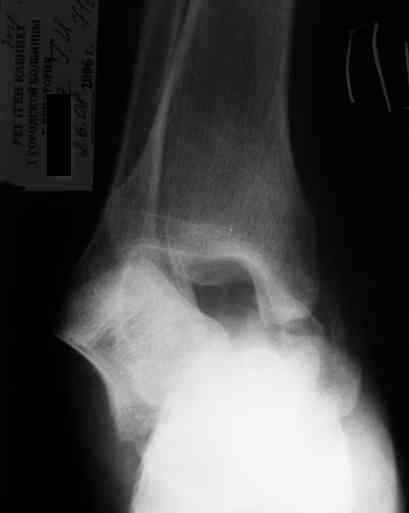

Уважаемый Александр! Как обещал представляю Р-граммы и операционные фото.

Ваши (лично ваши) рекомендации - астрагалэктомия-аппаратный пяточно-большеберцовый артродез с одновременным удлинением голени - правильно?

Можно убрать таранную кость, и поместить в образовавшуюся полость либо бусы из цемента с антибиотиками, либо вылепленный прямо по форме тарана спейсер. Целесообразность этого будет определяться распространенностью гнойного процесса. Может быть, будет достаточно только удаления тарана.

Вместе с аваскулярным куском кости устранится субстрат. Надо опасаться не мягких тканей, а плохо кровоснабжаемых. Если после удаления тарана добиться контакта хорошо васкуляризованных пятки и больщшеберцовой, мягкие ткани не давить, чтобы некроза раны не было, то все должно зажить.